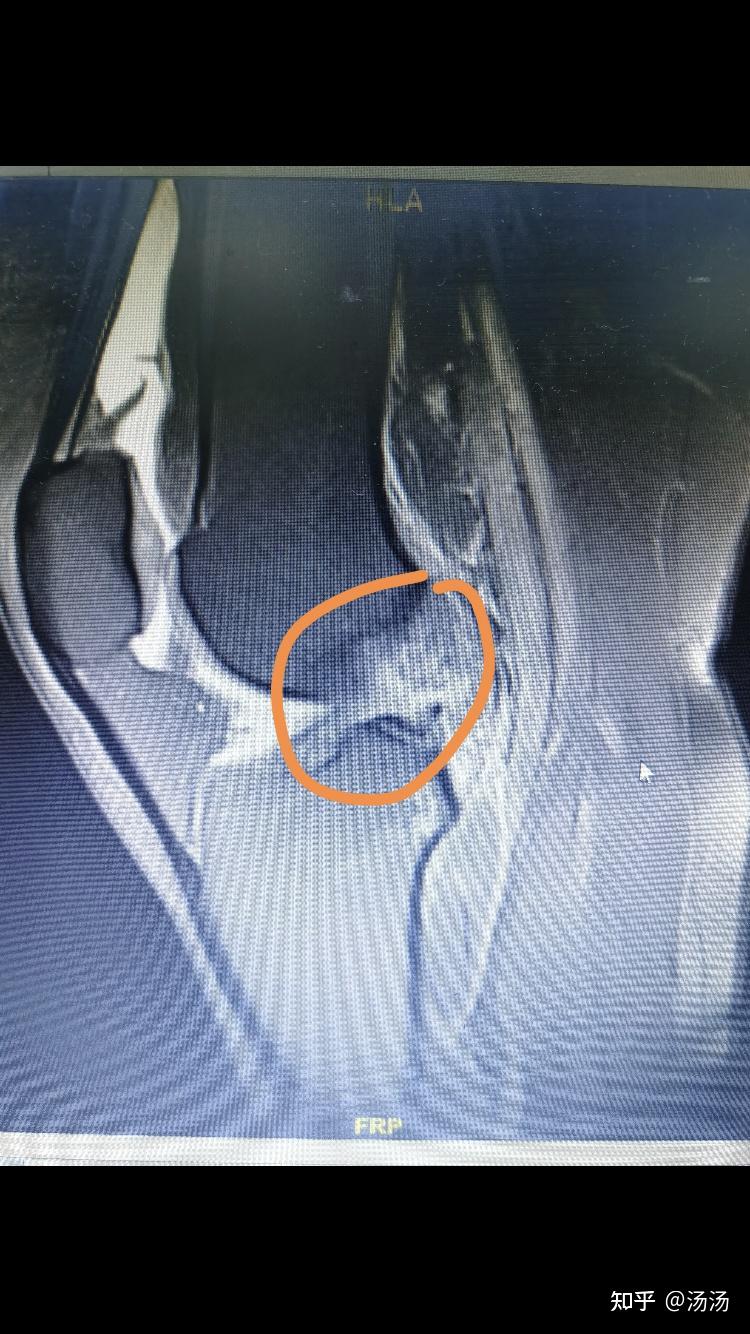

诊断:内侧半月板撕裂;前交叉韧带损伤.

半月板损伤?

右膝前叉韧带损伤半月板三度损伤